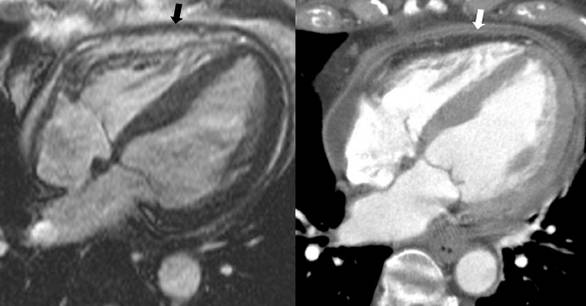

•CMR with intense delayed enhancement (red arrows) of the pericardium (left).

•After 6 weeks of prednisone therapy, the delayed enhancement was reduced (right).